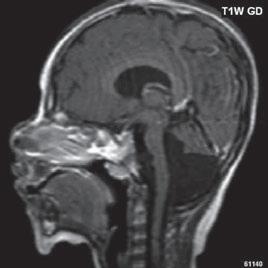

I.1.8 Dandy-Walkerova malformace (D-W variant, D-W komplex, D-W spektrum )

V současné odborné literatuře je nejčastěji užíván termín D-W spektrum, který snad nejlépe vyjadřuje velmi široké možnosti vrozených změn zadní jámy lební. Mezi tuto skupinu cystických malformací zadní jámy lební pak řadíme klasickou malformaci D-W a její varianty, mega cisterna magna, arachnoidální cystu zadní jámy lební a retrocerebelární vak (Blake’s pouch cysta). Zařazení malformace do určité klinické jednotky není někdy jednoznačné, proto je možná výhodnější a přesnější vycházet z přesného popisu zobrazených změn. Příčina D-W malformace není známa, nabízejí se dvě hypotézy: 1. nepropustná spodina IV. komory, eventuálně uzávěr nebo pozdní otevření otvorů, kterými proudí likvor ze IV. komory. 2. primární hypogeneze mozečku. Embryonální vývoj mozečku ze všech hlavních struktur mozku trvá nejdelší dobu, a proto je velmi vulnerabilní k různým patologickým příčinám po dlouhou dobu svého vývoje.

Zobrazení

D-W malformace je charakterizována hypoplazií vermis mozečku, rozšířením IV. mozkové komory, která se často cysticky vyklenuje dorzálně a může imitovat arachnoidální cystu, rozšířením zadní jámy lební a vysokým úponem tentoria s confluens sinum nad lambdovým švem. Okcipitální kost může být vlivem tlakových změn remodelována, existují i případy s porušením její kontinuity a encefalokélou. Hydrocefalus pozorujeme v 80 %, častá je přítomnost dysgeneze corpus callosum, schizencefalie.

D-W variant byl vyčleněn pro případy, kdy všechny základní příznaky nemusí být plně vyjádřeny nebo může některý zcela chybět. Bývá přítomna hypoplazie mozečku, což je dominantní příznak, IV. komora je obvykle rozšířena, někdy pozorujeme, že tvarem připomíná na axiální řezu „klíčovou dírku“, zadní jáma lební naopak rozšířena nebývá.

Obr. I.1.8a Dandy-Walkerova malformace, rozšířená IV komora (tvar klíčové dírky)

Obr. I.1.8b Dandy-Walkerova malformace, rozšířená IV komora široce komunikující s cisterna magna, hypotrofie mozečku (snímky zapůjčeny z archivu prim doc MUDr M Mechla, Ph D, MBA)

Obr. I.1.8c Dandy-Walkerova malformace, rozšířená IV komora široce komunikující s cisterna magna, hypotrofie mozečku (snímky zapůjčeny z archivu prim doc MUDr M Mechla, Ph D, MBA); stejný pacient jako na obr I 1 8b

Obr. I.1.8d Dandy-Walkerova malformace, rozšířená IV komora široce komunikující s cisterna magna, hypotrofie mozečku, vysoký úpon tentoria (šipka) (snímky zapůjčeny z archivu prim doc MUDr M Mechla, Ph D, MBA); stejný pacient jako na obr I 1 8b, c